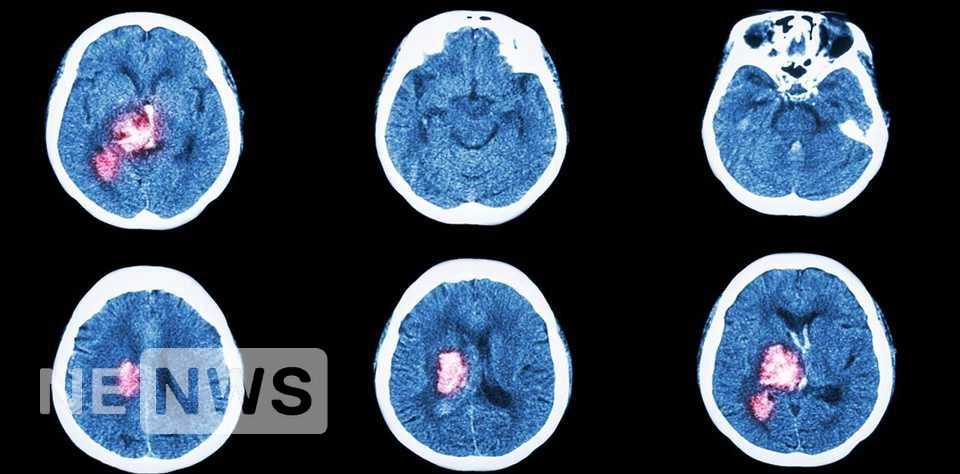

6. Втрачається зір в одному оці або відразу в обох. Інсульт – це порушення кровообігу мозку. Коли кров не надходить до клітин (через

тромб або розрив судини), вони гинуть. Через це людина втрачає здібності: рухатись, говорити, бачити, дихати. Інсульт – друга (після ішемічної хвороби серця) причина смертності. П’ята частина хворих після інсульту стає важкими інвалідами. Але багато наслідків можна запобігти, якщо вчасно викликати лікаря .